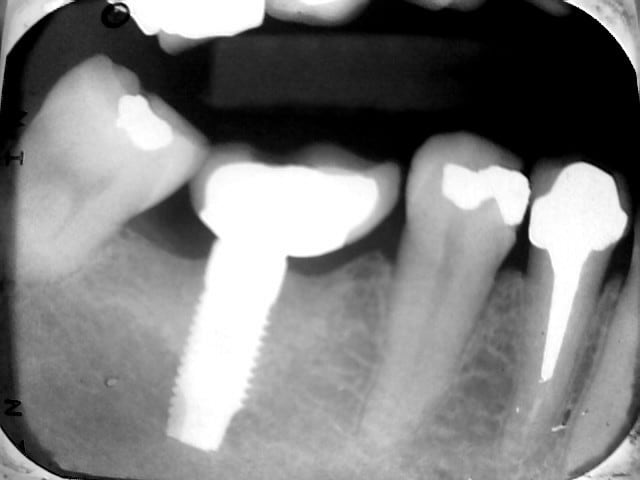

Confirmez.vous.que.cet.implant.est.bien.un.mis.?

Si.oui.de.quel.type?

Mis France...

Ta radiographie est floue, mal exposée....on peut même pas voir/deviner le type de connexion ( externe?interne?)....bref, inexploitable...